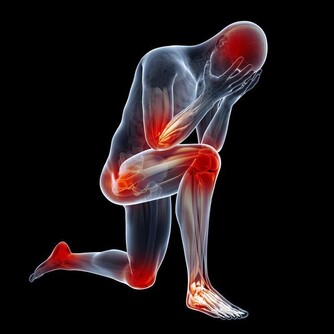

***三、痛風患者。***蝦屬於高嘌呤食物,容易加劇痛風症狀。